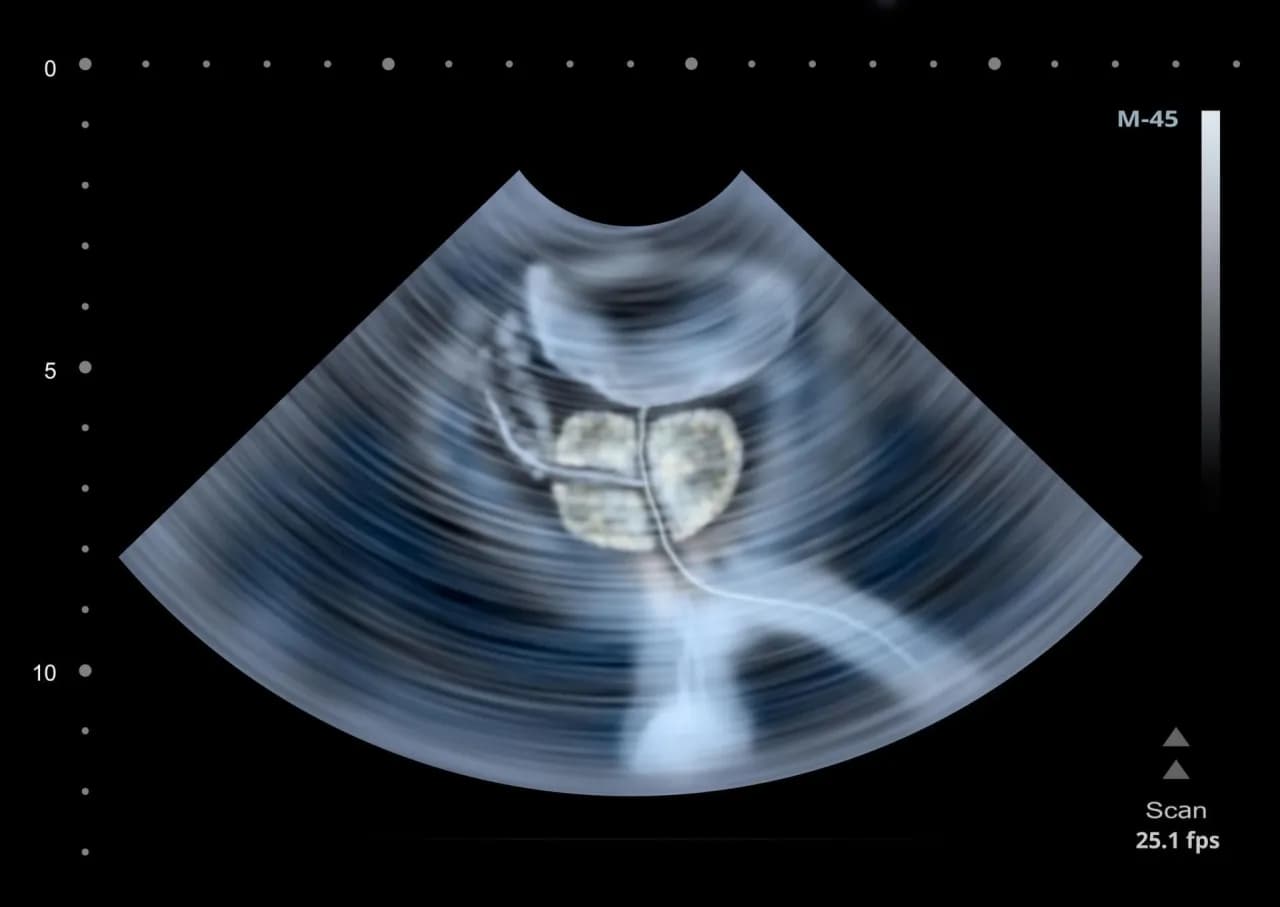

Kolejnym ważnym badaniem jest badanie PSA, które polega na pobraniu próbki krwi w celu pomiaru poziomu antygenu specyficznego dla prostaty. Wysoki poziom PSA może wskazywać na problemy zdrowotne, takie jak zapalenie prostaty lub nowotwór. Ultrasonografia transrektalna (USG TRUS) to metoda obrazowania, która wykorzystuje fale dźwiękowe do uzyskania obrazu prostaty, co pozwala na dokładniejszą diagnostykę. W przypadku podejrzenia nowotworu, lekarz może również zalecić biopsję prostaty, podczas której pobierane są próbki tkanki do analizy.

| USG TRUS | Obrazowanie prostaty | Diagnostyka nieprawidłowości |